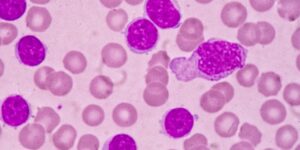

- Câncer de tireoide. O câncer de tireoide é muito menos comum do que os nódulos tireoidianos benignos. A biópsia de um nódulo tireoidiano é muito precisa para determinar se é cancerígena.